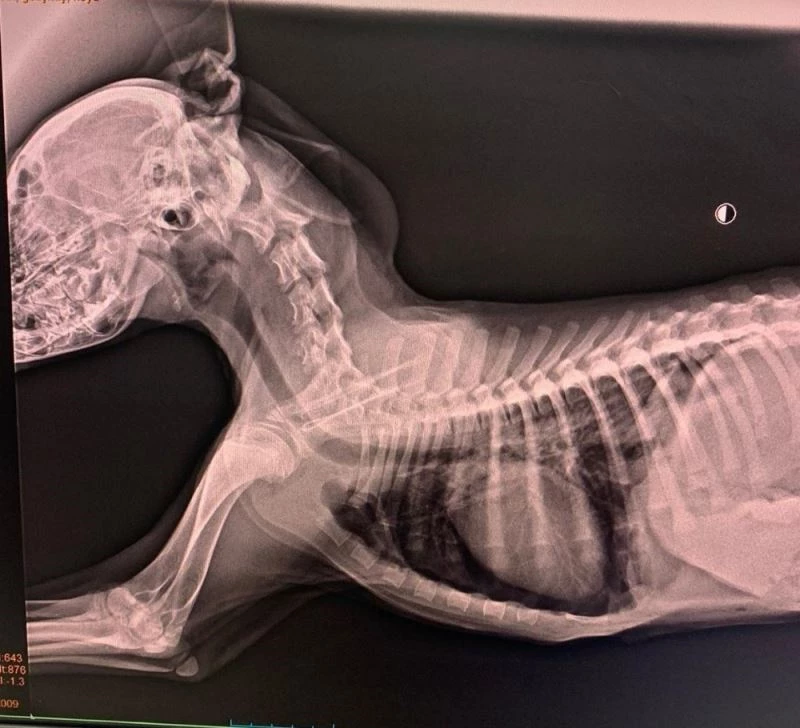

Düzce’nin Akınlar Mahallesi yolu üzerinde karşıdan karşıya geçmeye çalışan sokak köpeğine araba çarptı. Sürücü çarptığı köpeğin can çekiştiğini görünce hemen arabasına alıp Düzce Belediyesi Sokak Hayvanları Geçici Bakımevi ve Rehabilitasyon merkezine götürdü. Yaralı sokak köpeğine Düzce Belediyesi Veteriner İşleri Müdürlüğü’nde ilk müdahale yapılarak ameliyata alındı. Sokak köpeğinin bağırsaklarının kalbini sıkıştırdığı ve nefes almakta güçlük çektiği tespit edildi. Veteriner hekimler Ayşegül Aydın, Ufuk Göktaş ve Aykut Ekinci, sokak köpeğine yaklaşık 2 saatlik ameliyat sonrasında yeniden sağlığına kavuşturdu. Düzce Belediyesi Veteriner İşleri Müdürü Nurettin Özcan, “"Bir canı hayata döndürmenin mutluluğunu hekimlerimiz ile birlikte yaşadık. Başarılı bir operasyon gerçekleştirdiler, hekim arkadaşlarıma emekleri için çok teşekkür ediyorum" dedi.